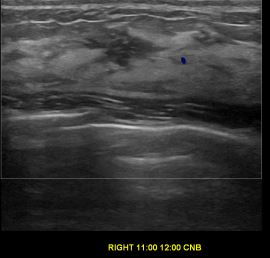

상기환자는 우측 유방통증으로 정밀검사위해 내원하신 30대 후반

여성분으로 의심스러운 우측유방혹 조직검사 시행해 제자리암으로 진단되었습니다